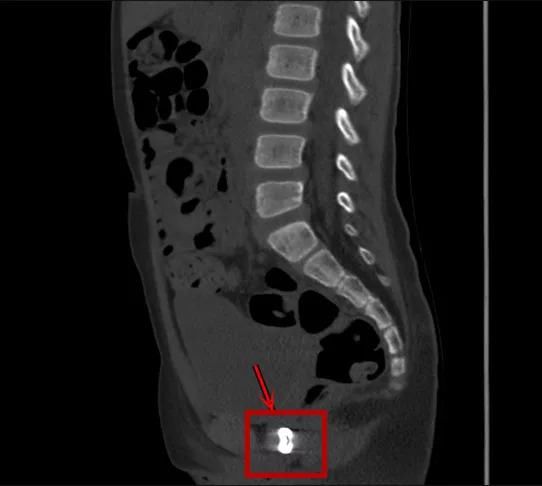

8岁·阴道异物

纽扣

半天前患儿反复诉会阴部疼痛,自诉经阴道塞入异物,家长说可能是纽扣。

文章图片